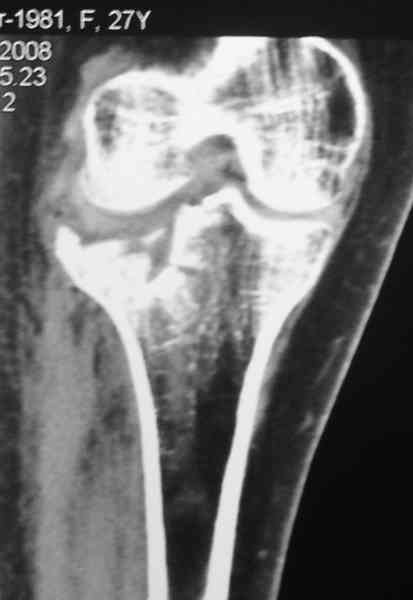

Re: Застарелый перелом 41С3

Уважаемый Абдурашид. Если нет противопоказаний , то из оперативных способов, я бы рекомендовал следующие: Полное замещение наружного мыщелка аллотрансплантатом либо открытая репозиция с элевацией и замещение дефекта ауто или аллокостью. В Ваших условиях , я бы рекомендовал второй способ. Во-время элевации необходимо разъединить фрагменты со стороны сустава ( надсечь скальпелем по линиям перелома, а затем тонким остеотомом их разъединить. При помощи долота произвести неполную остеотомию ( захватите не менее 1,5 - 2 см губчатой кости и поднять фрагменты, визуально отрепонировать и фиксировать 2-3 спицами. Дефект заместить костным ауто или аллатрансплантатом. Окончательная стабилизация пластиной ( лучше с угловой стабильностью, либо АВФ - позволит спокойно устранить угловую деформацию.

Недавно поступила больная через 1,5- 2 месяца.